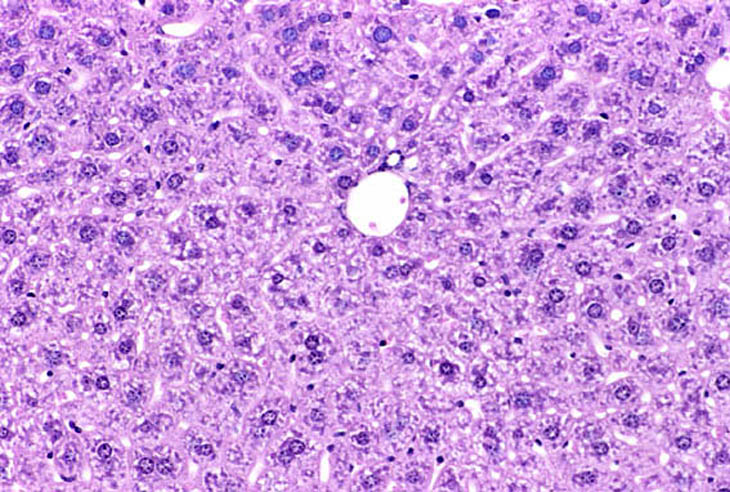

Immersion fixation in non-fasted mouse liver. Fixative was 10% NBF.